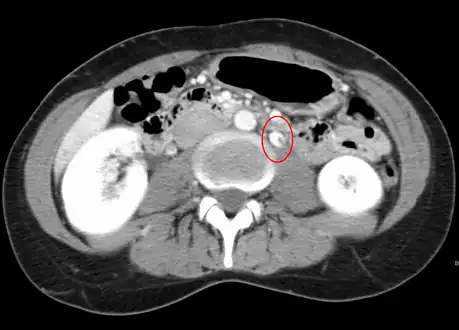

Nutcracker syndrome is diagnosed through imaging such as doppler ultrasound (DUS), computed tomography (CT), magnetic resonance imaging (MRI), and venography.[15] The selection of the imaging modality is a step-wise process. DUS is the initial choice after clinical suspicion based on symptoms. CT and MRI are used to follow up afterwards, and if further conrfirmation is necessary, venography is used to confirm.[15]

CT and MRI

CT and MRI can be used afterward to confirm compression by the AA and SMA with comprehensive measurements of the abdominal vasculature. A "beak sign" can often be seen in CT scans due to the LRV compression. However, CT and MRI cannot demonstrate the flow within the compressed vein. These two modalities can be used to confirm other evidence for NCS such as back-up of blood flow into the ovarian veins.[14][9]

If further confirmation is necessary, venography is used as the gold standard test in diagnosing nutcracker syndrome. A renocaval pullback mean gradient of >3 mmHg is considered diagnostic. Although this method continues to be the gold standard, values in unaffected individuals may be vary considerably, leading to some measurements in NCS patients to be similar to those in normal individuals.[15] This may be partly due to compensatory mechanisms in the vasculature as a result of the increased blood pressure. The invasive nature of the procedure is another consideration in comparison to DUS and CT/MRI as imaging modalities.[11]